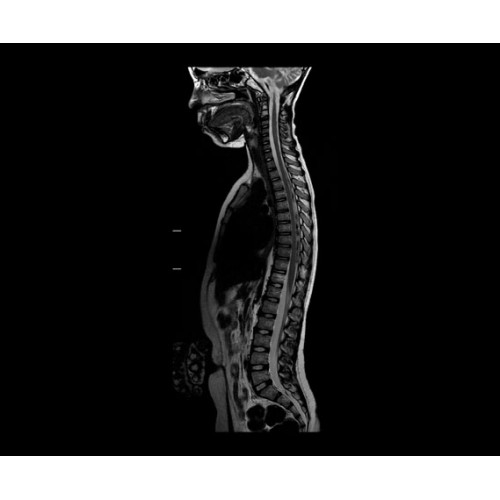

SIGNA PET/MR 3.0T — это гибридная система, в которой совмещаются две принципиально разные технологии — магнитно-резонансную томографию (МРТ) и позитронно-эмиссионную томографию (ПЭТ). Система отличающийся высокой чувствительностью и эффективностью и предназначена для диагностики в области онкологии, неврологии, кардио-васкулярных исследований, исследований воспалительных процессов.

Компания GE Healthcare представляет революционную, полностью интегрированную систему SIGNA PET/MR1, в которой сочетаются времяпролетная технология (TOF) и возможности напряженности магнитного поля 3.0 Тл. Мы поможем вам поднять исследования на более высокий уровень. SIGNA PET/MR позволяет достичь впечатляющей точности и скорости исследований, а благодаря новейшей технологии реконструкции Q.Clear2 качество изображений улучшается в два раза. Кроме того, в систему включен полный набор клинических приложений и гибких катушек для проведения любых видов исследования, открывая для вас возможности визуализации, о которых вы даже не догадывались.

Кроме того, в результате использования технологии TOF и инновационной технологии реконструкции Q.Clear вы сможете добиться прекрасного соотношения сигнал/шум. А благодаря технологии нулевого времени эхо (ZTE) визуализировать костную структуру без ионизирующего излучения. Все эти разработки для улучшения качества сканирования и точности анализа помогут вам использовать весь потенциал ПЭТ/МРТ.

• МРТ с функцией нулевого времени эхо (ZTE) отличается точностью, возможностью персональных настроек и отсутствием ионизирующего излучения. Она приходит на смену традиционному исследованию на основе рентгеновского излучения. МРТ с функцией нулевого времени эхо (ZTE) на базе SIGNA ПЭТ/МРТ является более надежной и быстрой по сравнению с системами, использующими сверхмалое время эхо (UTE).

• Специальный пакет приложений для измерения и сравнения объемных изображений ЦНС с нормами поможет вам в диагностике нейродегенеративных заболеваний, а дополнительные инструменты визуализации — в постановке точного диагноза с помощью бета-амилоидов и радиоизотопных маркеров ФДГ.